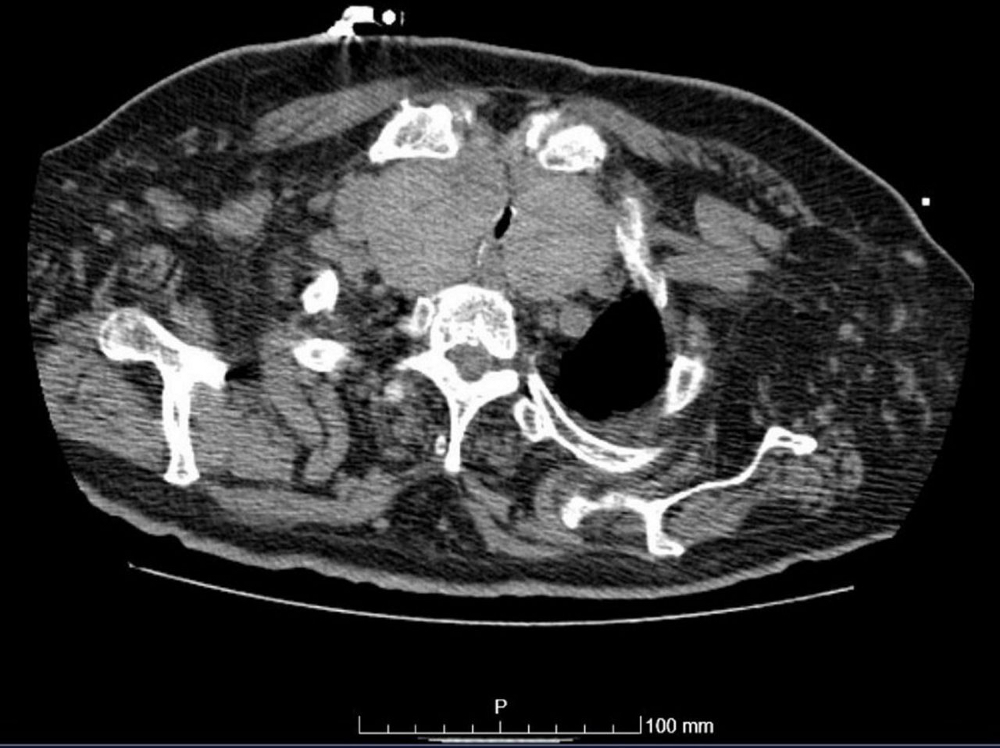

TC de tórax mostrando aumento acentuado da glândula tireoide com um extenso componente intratorácico causando compressão da traqueia

Dias T et al. Acute airway obstruction due to benign multinodular goitre. BMJ Case Reports. 2019;12:e228095; usado com permissão